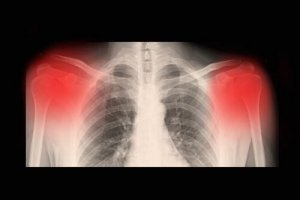

Vanligtvis kan diagnosen ställas efter kliniska tester. Normalt sett görs det med röntgen, datortomografi eller magnetröntgen. Hur allvarlig sjukdomen är kan även upptäckas via ett högupplöst ultraljud.